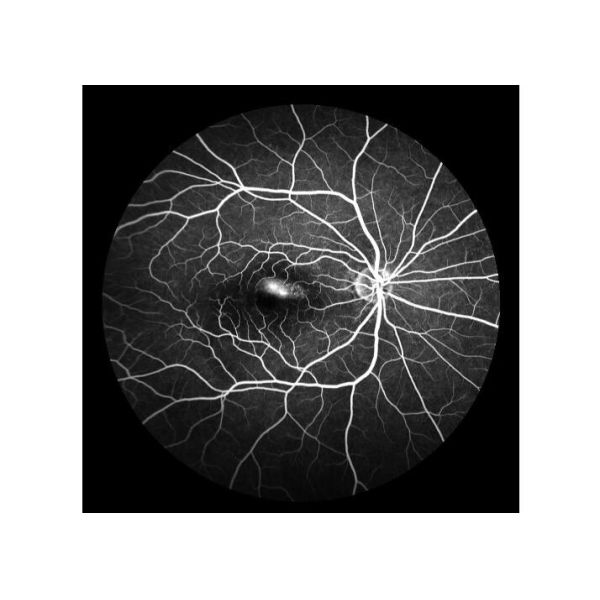

Infrarrojo (NIR) |

1) Para observar claramente la membrana anterior macular y el edema enquistado macular 2) Cómodo, ningún estímulo 3) El penetrar fuerte |